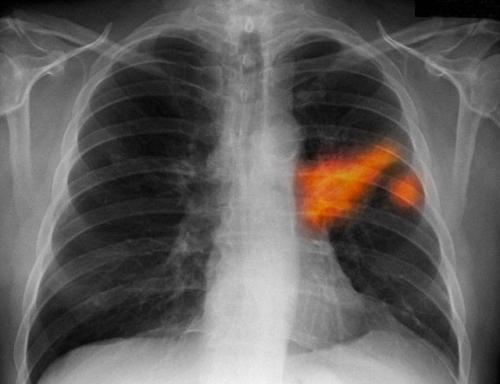

Old  Default Vợ bị mắc bệnh ung thư phổi chỉ vì thói quen hàng ngày của chồng

Câu chuyện về người phụ nữ đi khám phát hiện ra căn bệnh ung thư phổi được chia sẻ.Ngày nay,số người tử vong vì căn bệnh ung thư phổi ngày một nhiều mà nguyên nhân đều không phải do hút thuốc.Bác sĩ cho biết nguyên nhân chính dẫn đến bệnh ung thư phổi của phụ nữ từ thói quen hàng ngày của chồng.

Điều đáng nói, khi bệnh nhân nhập viện, các bác sĩ chẩn đoán một trong những nguyên nhân dẫn đến căn bệnh ung thư phổi của bà Nh. do phải hút thuốc lá thụ động. Điều này khiến bản thẩn bà và gia đình vô cùng sửng sốt.

Vị này khuyến cáo, thuốc lá là một trong những nguyên nhân của nhiều loại bệnh tật nguy hiểm, trong đó có ung thư phổi, nhồi máu cơ tim, xơ vữa động mạch và các bệnh về hô hấp. Điều đáng nói là hút thuốc không chỉ ảnh hưởng trực tiếp đến người hút mà khói thuốc còn ảnh hưởng nghiêm trọng đến sức khỏe của những người xung quanh.

Theo bác sĩ Vũ Hải - bệnh viện K Trung ương, nhiều công trình nghiên cứu cho thấy, mối liên quan giữa bệnh ung thư phối với tác nhân thuốc lá. Đây là nguyên nhân hàng đầu gây ung thư phổi.